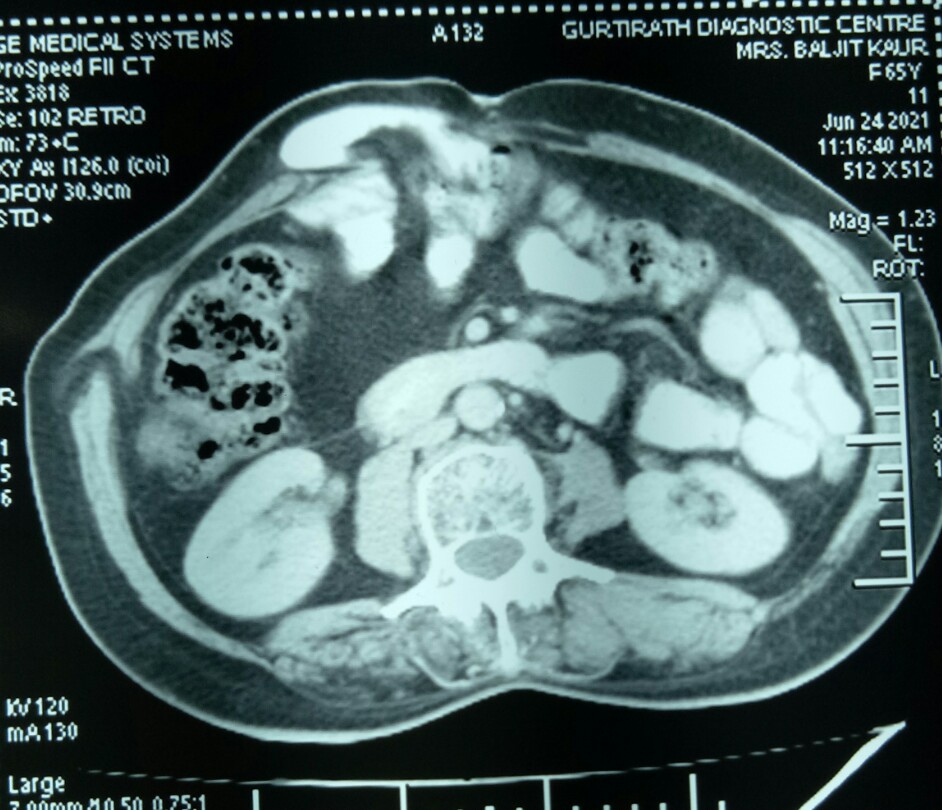

CT scans confirmed grossly dilated small bowel loops in the pelvis and left flank and one jejunal loop high in the centre, besides showing a mass of dense adhesions just under the staple line of the hernia surgery.